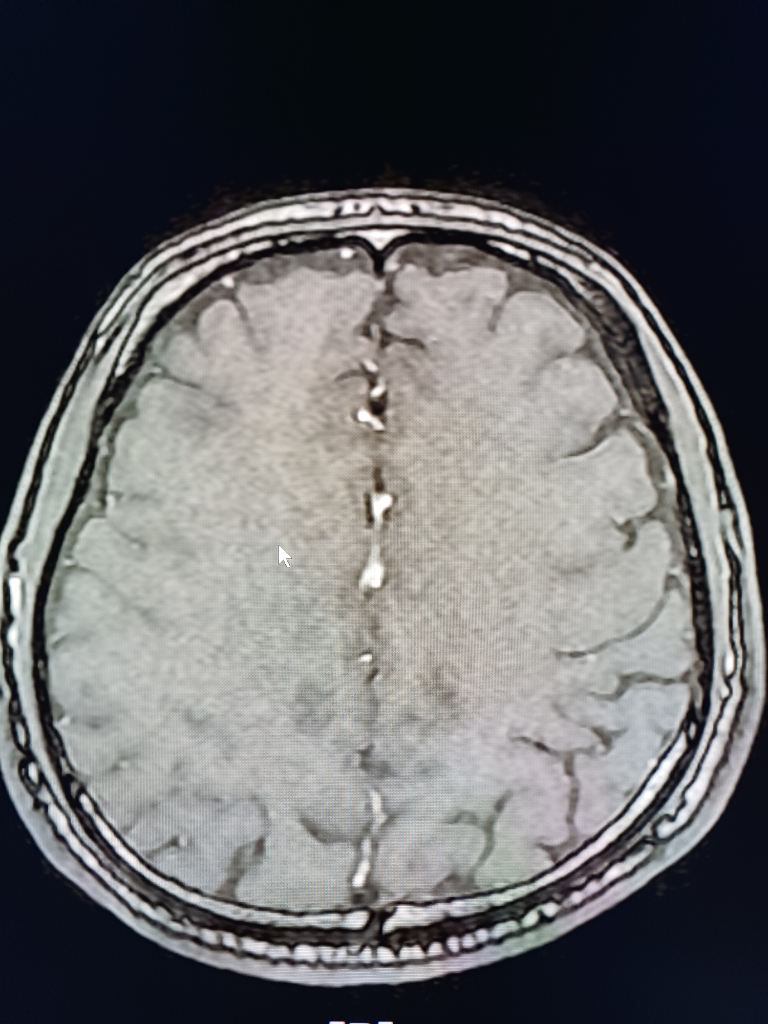

뇌 mri mra를 찍었는데 전문가분들의 고견을 구합니다.

안녕하세요.불편한 어지러움이 한달이상 지속되어 혹뇌쪽 이상이 아닌가 싶어 오늘급하게 mri mra를 촬영하고 왔습니다.결과를 바로 확인할수 있는줄 알았으나 일주일정도 기다려야 판독이 나온다하여 급한 마음에 사진 몇장 첨부하오니 답변해주시면 감사하겠습니다!!

• 4번 째 사진

업로드해주신 MRI 및 MRA 영상은 특별히 이상한 소견이 보이지 않습니다

뇌실질에 이상소견 없으며 뇌혈관이 막여있거나 좁아진 부분도 보이지 않습니다

현재 올려주신 사진만으로는 아주 큰 병변 이 있어 보이지는 않으나, MRI의 경우 연속된 단면을 모두 봐야 병변을 정확히 확인할 수 있으므로 해당 사진들만으로는 병변의 유무를 모두 다 확인 불가능합니다. 추후 판독을 기다려 보시기 바랍니다.